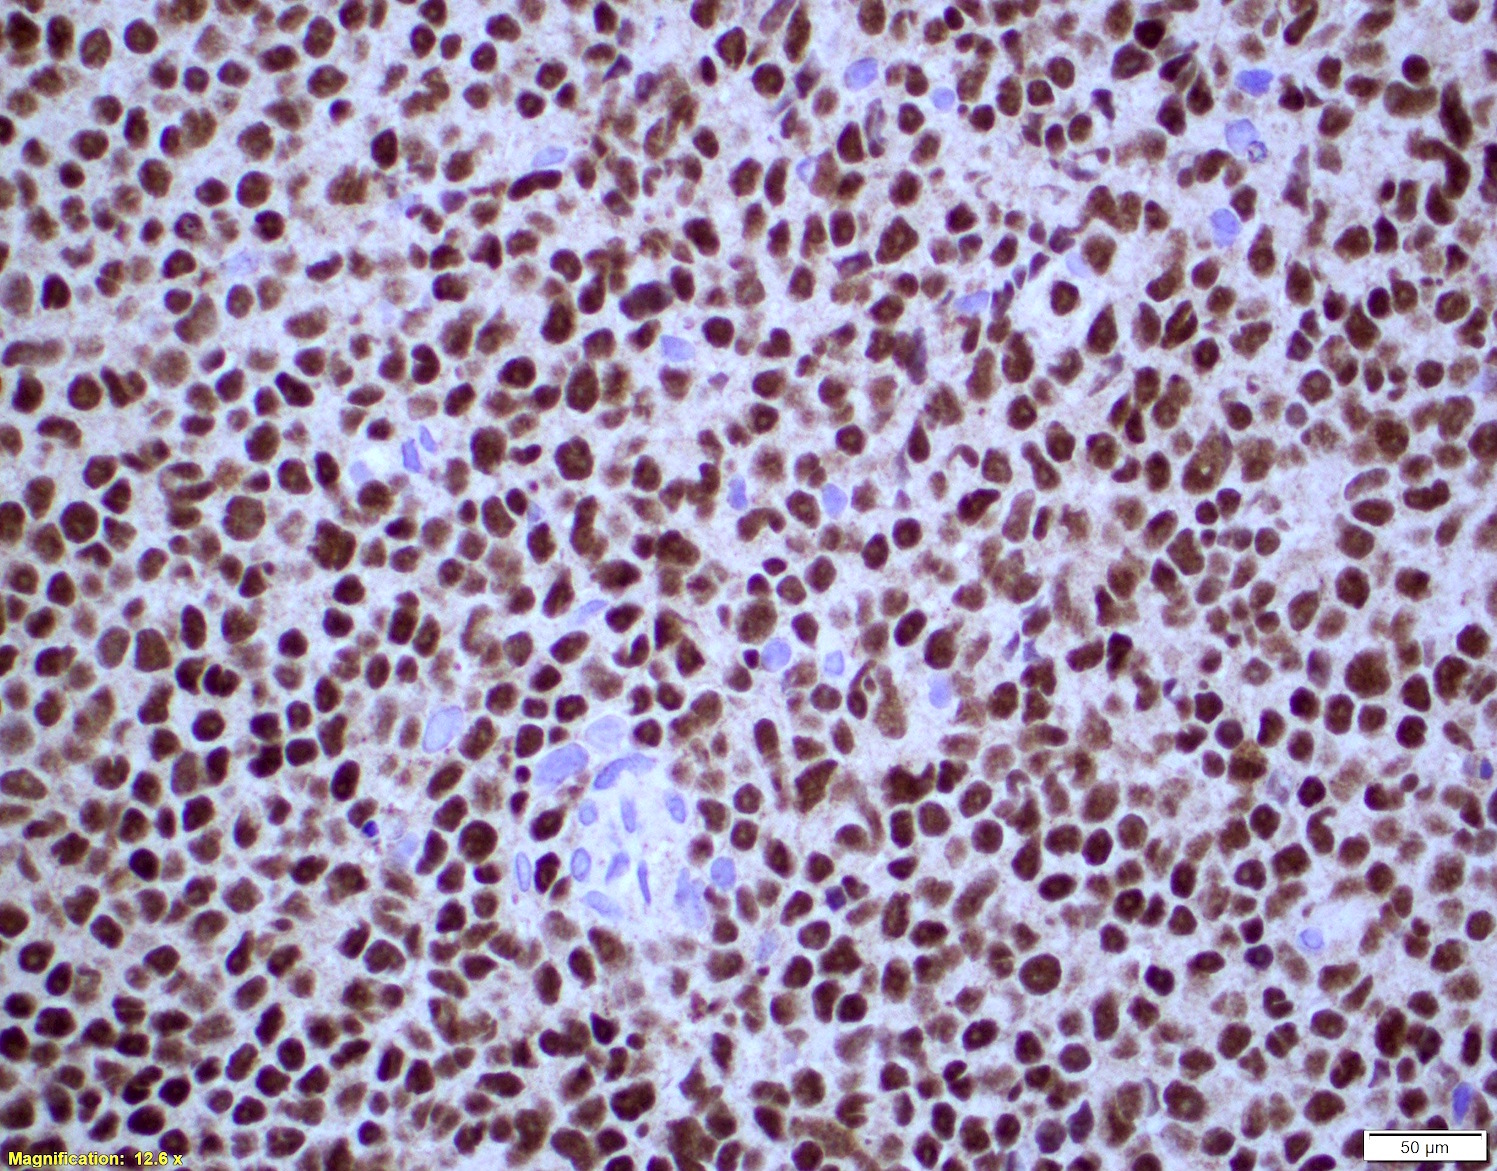

- High cell proliferation (Ki67), 30% cutoff (J Clin Oncol 2016;34:1386)

- Note: Ki67 index overrides the prognostic significance of the cytology subtype (J Clin Oncol 2016;34:1386)

- Ki67 count (J Hematop 2009;2:103)

- Five independent high power fields count

- Avoidance of residual germinal centers, hot spots and proliferating T cells

- Note: Ki67 index is not sufficient to classify as blastoid or pleomorphic subtype

- Classical mantle cell lymphoma might also show high cell proliferation (Blood 2008;111:2385)